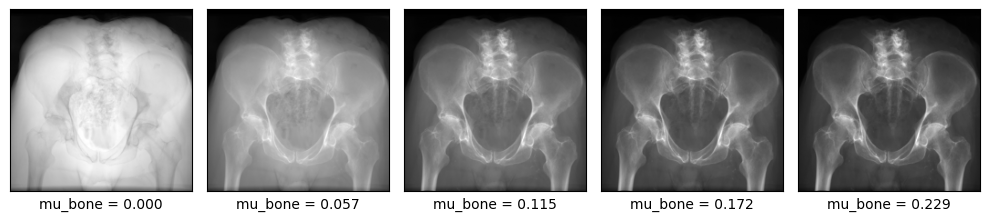

Contrast variation¶

Physically-accurate rendering requires the voxelgrid to be in units of linear attenuation coefficients (LACs).

Conversion from CT's Hounsfield Units (HUs) to LACs is handled by nanodrr.data.preprocess.hu_to_mu.

When a subject is initialized, this conversion is performed and the resulting LAC tensor is cached. If you

change any of these values on the fly (e.g., subject.mu_bone = 1.0), the LAC tensor is recomputed. This

let's you vary the contrast of the rendered X-rays, which is a useful data augmentation.

from nanodrr.data.preprocess import MU_BONE

subject = Subject.from_filepath(imagepath, mu_bone=MU_BONE).to(device)

rt_inv = make_rt_inv(

torch.tensor([[0.0, 0.0, 0.0]], device=device),

torch.tensor([[0.0, 850.0, 0.0]], device=device),

orientation="AP",

isocenter=subject.isocenter,

)

imgs = []

bmus = []

for multiplier in range(0, 5):

subject.mu_bone = multiplier * MU_BONE

img = drr(subject, rt_inv)

imgs.append(img)

bmus.append(subject.mu_bone)

plot_drr(torch.cat(imgs), ticks=False, title=[f"mu_bone = {bmu:.3f}" for bmu in bmus])

plt.tight_layout()

plt.show()